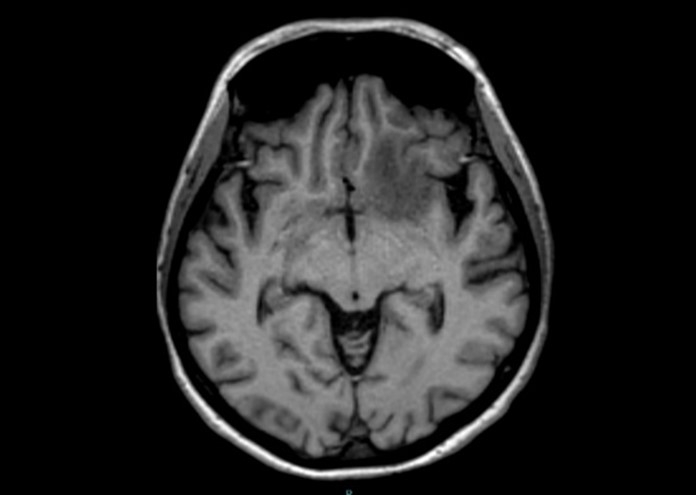

Result of MRI was at T1WI hypointense lesion as seen on (Figure 4), at fluid sensitive sequences T2WI \ FLAIR the lesion is hyperintense as shown in (Figure 5), after GAD enhancement there's irregular ring enhancement of the lesion (Figure 6). Followed by vasogenic edema that is visible in flair sequence at the medial aspect of base of frontal lobe that also affects the head of caudate nucleus. No diffusion restriction was seen in DWI and ADC sequences (Figure7a,7b). In SWI there's no detection of blood products.

Figure 4: Axial T1WI shows hypointense lesion at the LT frontal lobe.